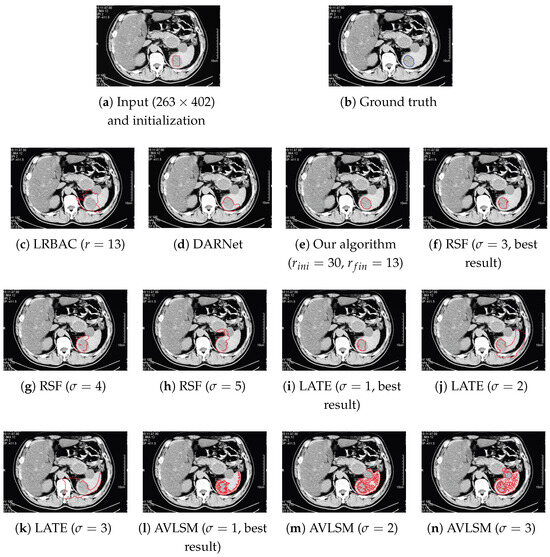

There are several drawbacks in the existing localization (active contour) models. Some models have poor capability of handling uneven illuminations and low contrasts, others are sensitive to initial condition, and there are still some models which can not converge to the object boundary stably. In this paper, following the routes of Localizing Region-Based Active Contours (LRBAC) which is an important localization method, we propose a new localized active contour model. By altering the underlying construction logic, our proposed algorithm overcomes the problem of LRBAC with respect to poor convergence stability. Compared with some state-of-the-art localization models, our new algorithm is more similar to an edge-based one and therefore performs better when handling uneven illuminations and low contrasts. Moreover, combining the features of the region-based and the edge-based active contours, we propose, for our algorithm, a simple approach to dynamically control the localization size. This dynamical method makes our algorithm more robust to the initial condition. Detailed theoretical analysis and comparison are presented to clarify the features of our proposed algorithm. Experimental results on real-image segmentation underline the effectiveness of our proposed algorithm. Full article

Show Figures

Figure 1